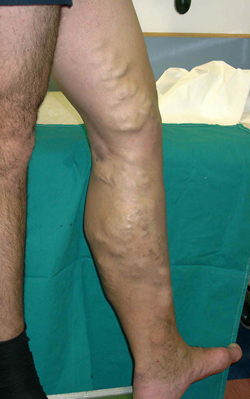

ΚΙΡΣΟΙ

ΚΑΤΩ ΑΚΡΩΝ

των βαλβίδων. Μεγάλη κλινική αξία έχει η παλινδρόμηση παρά τη σαφηνομηριαία

συμβολή και υποδηλεί ανεπάρκεια της σαφηνομηριαίας βαλβίδας, με κλινική εμφάνιση

κιρσοειδών ανευρύνσεων στο σύστημα της μείζονος σαφηνής φλέβας. Επί ανεπάρκειας

των βαλβίδων των αναστομωτικών φλεβών, φλεβική παλινδρόμηση ανιχνεύεται στα

σημεία των αναστομωτικών φλεβών, με κλινική εμφάνιση διευρυσμένων φλεβών και

κιρσών σε άλλα σημεία του επιπολής φλεβικού συστήματος, στα οποία ευρίσκονται

οι αναστομωτικές ανεπαρκείς φλέβες. Επίσης, παλινδρόμηση ανιχνεύεται στο εν

τω βάθει φλεβικό δίκτυο επί ανεπάρκειας ή αδράνειας των βαλβίδων, κυρίως στο

μεταφλεβιτικό σύνδρομο, όπου οι βαλβίδες λόγω της προϋπάρχουσας θρόμβωσης δεν

συγκλείονται και παραμένουν ακινητοποιημένες και εφόσον φυσικά επέλθει επανασηραγγαποίηση

του εν τω βάθει φλεβικού δικτύου. Εάν φυσικά υπάρχει δίοδος προς το επιπολής

δίκτυο και οι αναστομωτικές φλέβες ανεπαρκούν, επίκειται η εμφάνισης δευτεροπαθών

κιρσών. Στις αρτηριοφλεβώδεις επικοινωνίες, η αιματική ροή επί των φλεβικών

τμημάτων ανιχνεύεται καθαρά αρτηριοποιημένη και σαφώς με έντονη παλινδρόμηση.

Όσο απομακρυνόμαστε από το σημείο της επικοινωνίας, τόσο ομαλοποιείται η αιματική

φλεβική ροή, και επί υγιών βαλβίδων περιορίζεται η έκταση της βλάβης. Πληροφορίες